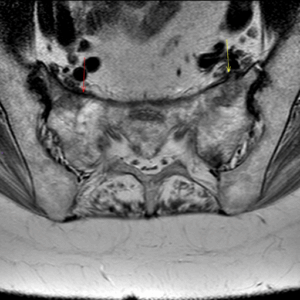

Figure 4: MRI showing sacral insufficiency fracture on background of osteoporosis and parathyroidectomy

Figure 5: MRI showing sacral insufficiency fracture on background of osteoporosis and parathyroidectomy

Figure 6: MRI showing sacral insufficiency fracture on background of osteoporosis and parathyroidectomy